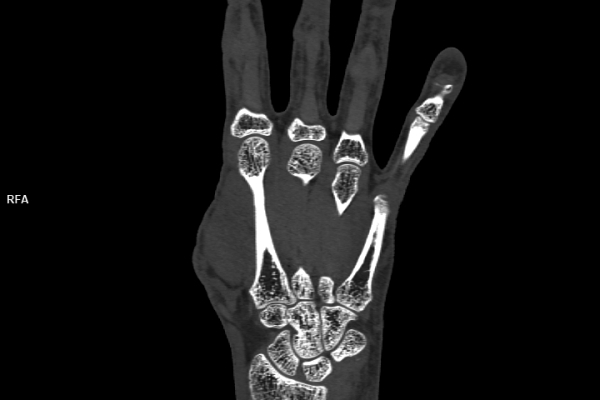

CT Untersuchung Bild

Detailbild MRT